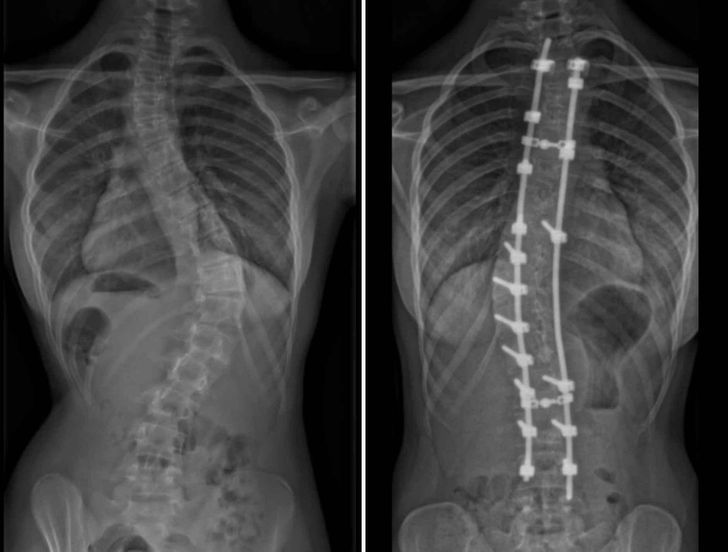

Hat éve volt a műtétem..